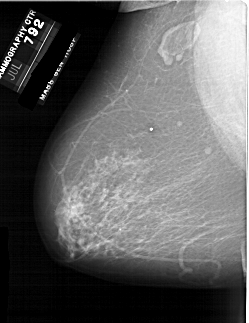

A_1861_1.LEFT_CC

LEFT_CC LINES 6871 PIXELS_PER_LINE 4306 BITS_PER_PIXEL 12 RESOLUTION 43.5 NON_OVERLAY